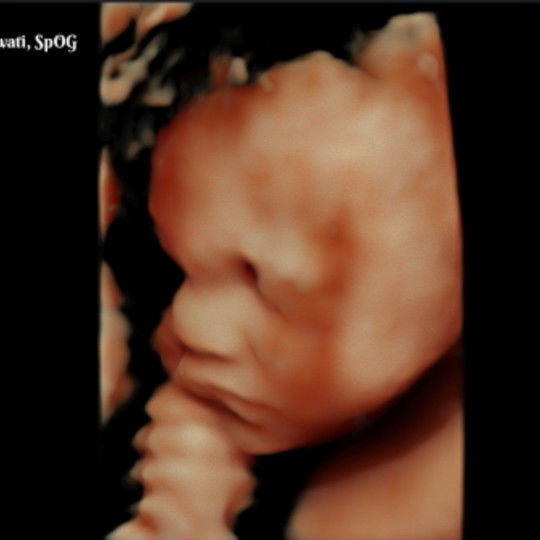

baby girl

Td pagi kontrol USG , seneng baget bisa lihat wajah si adek yg lucu , mirip papa banget padahal cewek, semoga selalu sehat ya nak ?